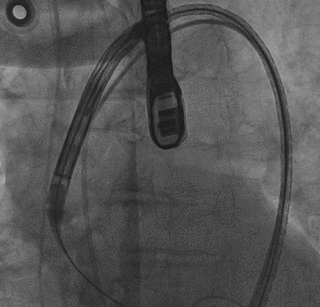

陈灏教授团队总结了该病例特点:三叶瓣,纯返流,瓣环周长68mm,LVOT周长70.9mm,LCA/RCA分别高15/9mm,STJ最大直径29.8mm,考虑纯返流病例,瓣膜锚定难度大,术中或术后可能出现瓣膜移位等严重并发症,瓣膜的精准定位和稳定释放极为关键。经反复评估,考虑VitaFlow Liberty可回收电动输送系统可以实现快速稳定且精准的释放、回收及瓣膜锚定,且瓣膜的双层裙边设计在减少瓣周漏的同时增加锚定摩擦力。oversize选择VitaFlow27瓣膜。

术中操作

顺畅过弓

瓣膜开始释放